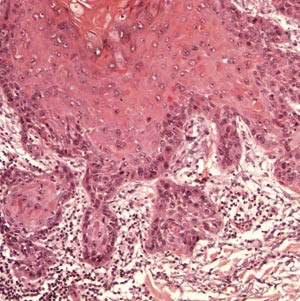

Morfologiske holdepunkter for plateepitelneoplasi

Aktinisk keratose har forskjellige presentasjonsformer. Lesjonen er begrenset til epidermis og gjenkjennes ved tap av cellenes polaritet, cytologisk atypi og enkelte mitoser (e-fig 1, fig 2, fig 3). De atypiske keratinocyttene finnes oftest nær basallaget (e-fig 1), men atypiske epitelceller kan også finnes i andre lag av epidermis når lesjonen progredierer (fig 2, fig 3). På overflaten er de atypiske keratinocyttene dekket av hyperkeratose og parakeratose, noe som gjør at epidermis blir fortykket når lesjonen blir mer avansert.

Grensen mellom dysplastiske og normale keratinocytter er ofte skarp. De atypiske keratinocyttene danner ofte tappformede nedvekster fra basallaget som kan gå over i svettekjertler og hårfollikler uten gjennomvekst av basalmembranen. De vanligste formene er atrofisk, hypertrofisk, bowenoid og lichenoid. Den atrofiske varianten har ofte lettere atypi, mens den hypertrofiske og den bowenoide er karakterisert ved grov atypi og manglende polaritet i hele epitelet, som ved cancer in situ. Bare manglende infiltrasjon gjennom basalmembranen skiller hypertrofisk og bowenoid form fra plateepitelkarsinom (fig 4).